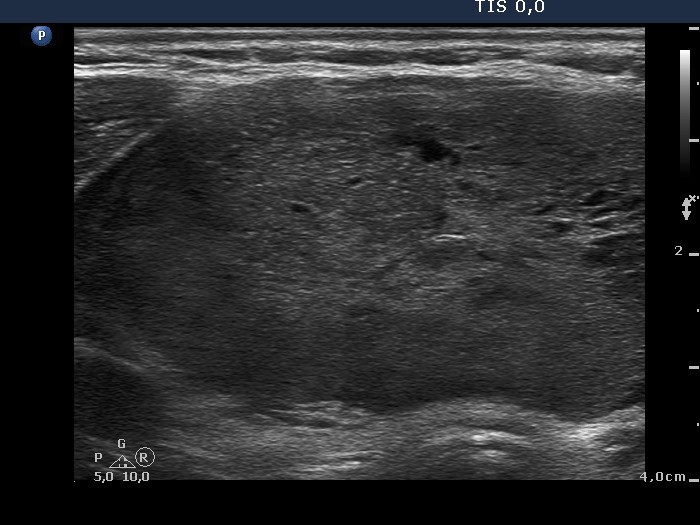

Ultrasonography. The thyroid was echonormal and presented several discrete hypoechogenic lesions. There was a large moderately hypoechogenic nodule in the isthmus. The nodule did not display halo but did perinodular blood flow.